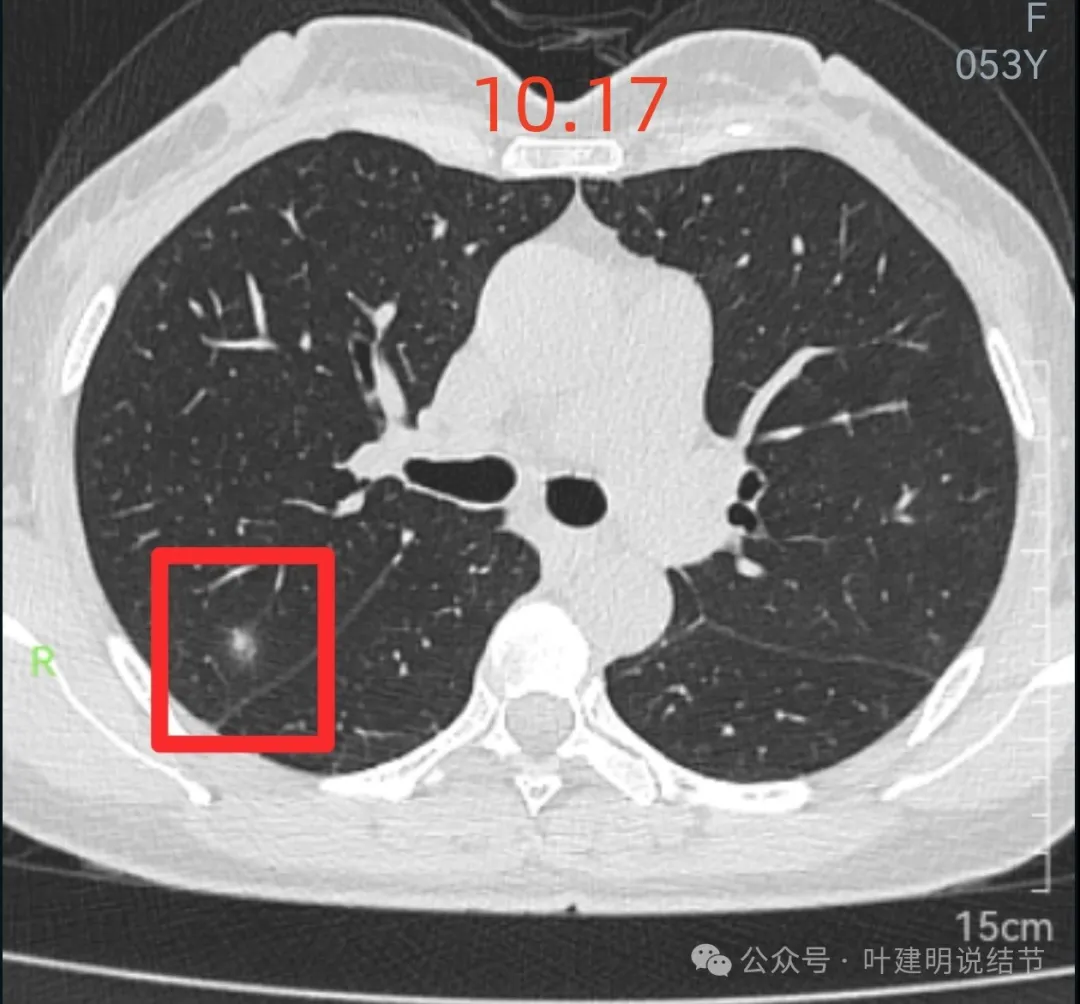

先来看2024年10月16日的影像:

右上后段混合密度结节,瘤肺边界欠清,有明显实性成分,边缘不光滑。

右肺很淡的磨玻璃阴影,伴进入的血管异常增粗,整体轮廓尚显清楚。

右下叶背段边界欠清的磨玻璃影,有血管刚好位于病灶处。

再来看周教授认为4B类的右上后段病灶连续层面影像信息:

病灶出现,轮廓不清,瘤肺边界模糊,有血管穿行,血管有异常增粗。

血管壁有异常密度增高,病灶混合密度,轮廓总体在此层较清,但瘤肺边界不清。

病灶偏实性部分不密实,磨玻璃部分过淡且模糊。

边缘有毛刺,但不够锐利;外周磨玻璃成分密度过淡且界限不清;实性部分也显得不致密;与叶间裂距离近但没有任何牵拉影响。

实性成分在灶内看,也是界限不清,磨玻璃部分淡而糊。

整体感觉像病灶中间偏实性些的成分伴外周晕征。

边缘区域离叶间裂更近,仍无牵拉。

几乎贴着叶间裂了,仍无任何牵拉影响。

病灶密度边缘部分也不均,离叶间裂近而没有影响。

上图病灶已经贴着叶间裂,但仍显示是平直的,没有任何牵拉影响。

矢状位上看,病灶虽整体轮廓较清,但瘤肺边界显模糊,整体不致密。

冠状位上看病灶有实性成分,实性成分缺乏收缩力,外围是淡磨玻璃成分,瘤肺边界欠清,贴着叶裂没有影响。

从连续层面以及影像细节上看,这个病灶就不可能是恶性的!短期内出现,混合密度而瘤肺边界不清,整体缺乏收缩力也无膨胀性,灶内实性成分不致密且磨玻璃成分过淡,灶内血管有异常增粗与密度过高,又是两肺多发病灶。这所有的表现与病情发展都与感染性病变契合,周围淡磨就是炎症水肿的关系,血管异常就是管壁有炎症的关系,多发就是感染(致病因素)影响两肺的关系。怎么可能是恶性?